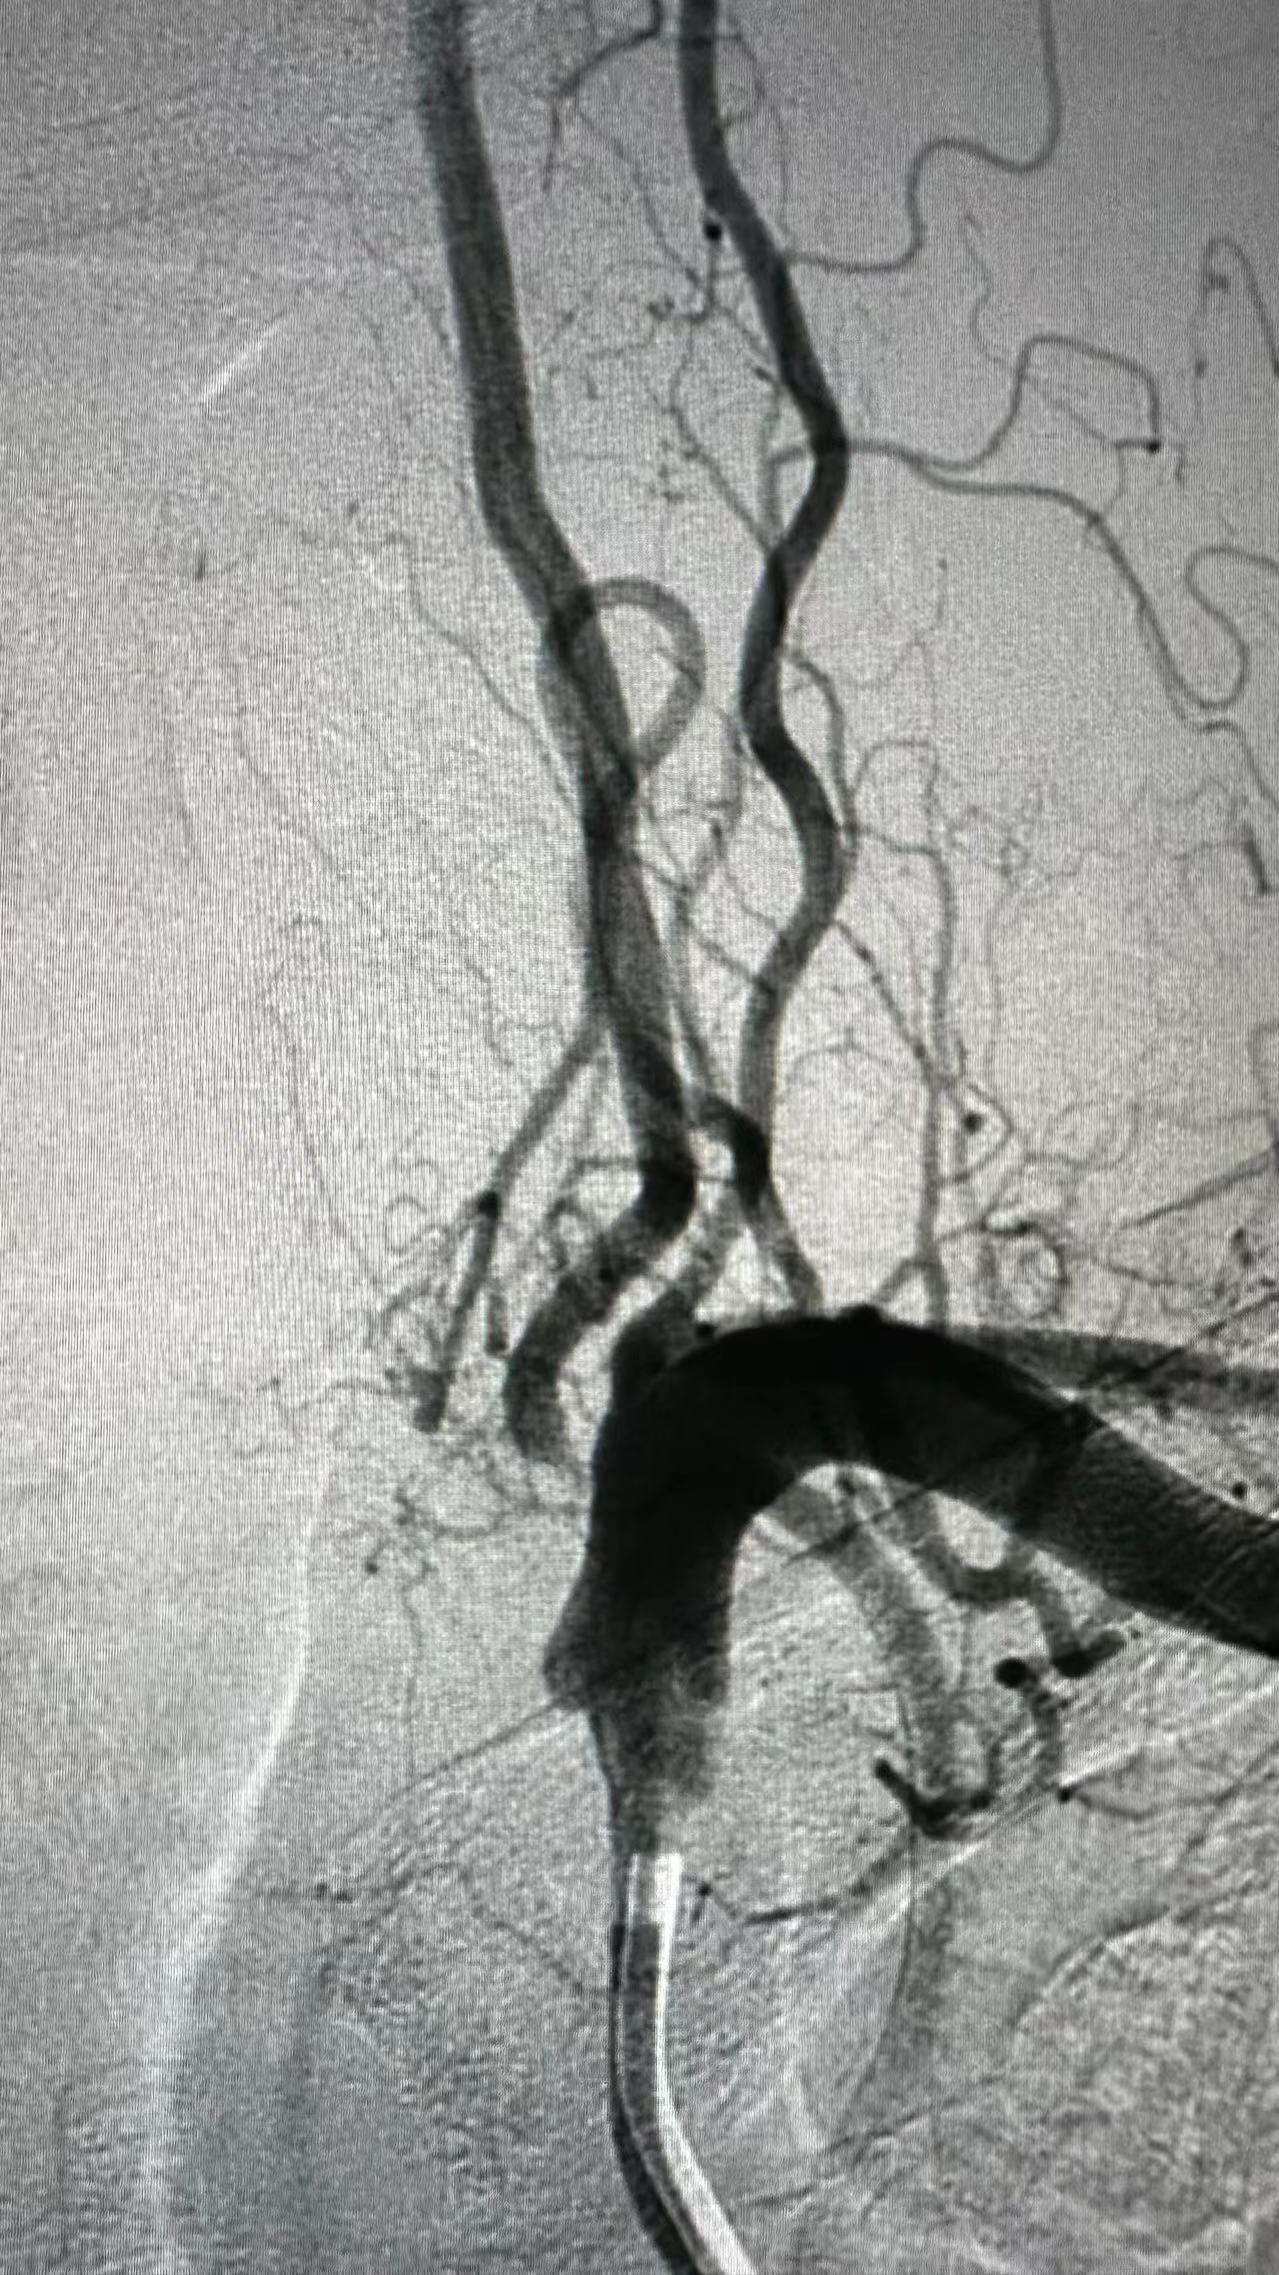

丽江市人民医院老年病科神内团队在6月28日上午成功为患有脑梗死的和大爷进行了脑血管支架置入手术。这一手术顺利进行,术后和大爷恢复良好,并有效地预防了再次发生脑中风的可能。 该团队针对老年科住院患者常常伴随多种疾病,且年龄较大,风险较高,手术难度较大的特点,积极完善术前评估和准备工作,确保患者的安全,成功完成了手术。他们让多病共患的老年患者能够在家门口得到有效的治疗,避免了患者转院造成的困扰,也减轻了患者家庭的负担。 下一步,老年科团队将针对丽江市人口老龄化、多病共患以及心脑血管疾病多发的情况,积极开展血管内微创诊疗工作,实现心脑同检和治疗。他们将充分利用自身优势,结合神经介入和心血管介入技术,进行经桡心血管和脑血管诊疗,提高患者的安全性和舒适度,为患者提供一站式的医疗服务。 |

6月28日上午,丽江市人民医院老年病科神内团队成功为患有脑梗死的和大爷进行了脑血管支架置入手术。这次手术非常顺利,术后大爷恢复良好,并有效地减少了再次发生脑中风的风险。 由于老年病科住院患者多病共患且年纪较大,手术的风险和难度较高。为了确保患者安全,老年科神内团队在术前进行了充分的评估和准备工作,并成功完成了手术。这样一来,多病共患的老年患者能够在家门口得到有效治疗,避免了转院的劳累和患者家庭的经济负担。 下一步,老年科团队将继续针对丽江市人口老龄化、多病共患和心脑血管疾病多发的特点,积极开展血管内微创诊疗工作,实现心脑同检和心脑同治。他们将利用团队的优势结合神经介入和心血管介入技术,提高患者的安全性和舒适度,并提供一站式的医疗服务。 这次成功的手术不仅解决了大爷的"头"等大事,也展示了丽江市人民医院老年病科专家团队的实力和医疗水平。希望他们能在未来继续为广大患者提供更好的医疗服务。 |